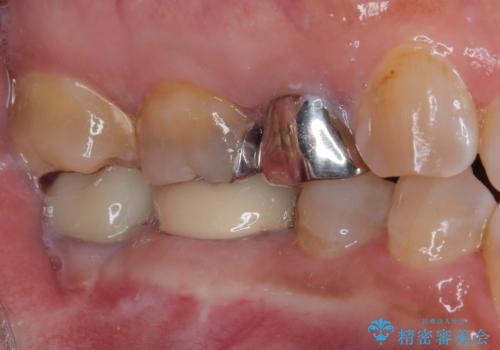

仮歯に替えた上で、速やかにオールセラミッククラウンにて補綴治療を行うこととしました。

銀歯を外したところ、土台にほとんどむし歯はなかったため、土台のやり替えを行うことなく、セラミッククラウンを装着しました。